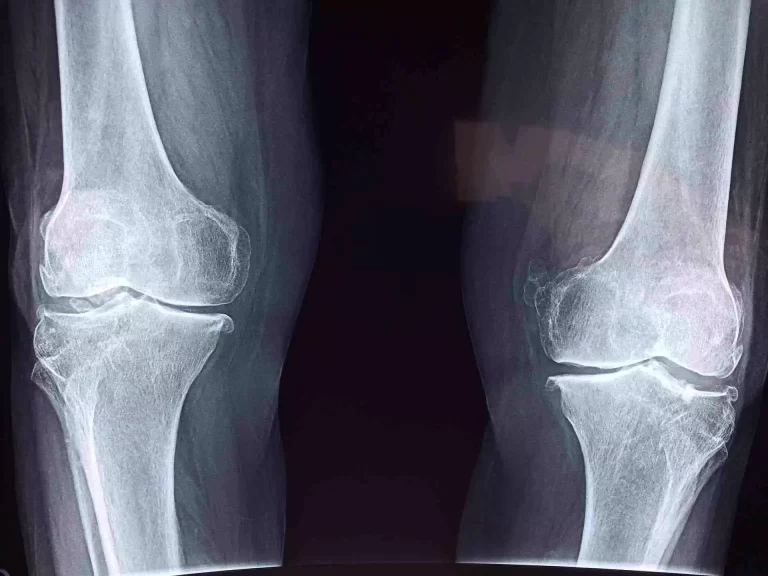

Kinesio taping telah terbukti efektif dalam menangani berbagai cedera sendi, termasuk sprain pergelangan kaki, dislokasi bahu, nyeri lutut akibat overuse, dan cedera punggung bawah. Selain itu, kondisi seperti bursitis, tendinitis, dan nyeri sendi akibat osteoartritis juga merespons dengan baik terhadap aplikasi kinesio tape. Teknik ini sangat berguna dalam fase sub-akut hingga pemulihan, di mana pasien masih membutuhkan stabilisasi, tetapi sudah diperbolehkan mulai bergerak secara bertahap. Penerapan kinesio tape menjadi salah satu solusi non-invasif yang bisa mendukung perbaikan fungsi sendi secara signifikan.

Berbagai penelitian telah mendukung manfaat kinesio taping dalam pemulihan cedera. Sebuah studi yang diterbitkan oleh Universitas Muhammadiyah Surakarta membuktikan bahwa penggunaan kinesio taping pada atlet yang mengalami cedera pergelangan kaki mampu mempercepat proses pemulihan dan meningkatkan stabilitas dinamis (sumber jurnal). Studi lain dari lingkungan rumah sakit olahraga menunjukkan pengurangan signifikan dalam rasa sakit dan pembengkakan pada pasien osteoartritis lutut setelah penerapan kinesio taping selama dua minggu. Temuan ini menguatkan bahwa KT bukan sekadar alat pendukung, tetapi bagian penting dalam strategi pemulihan sendi.